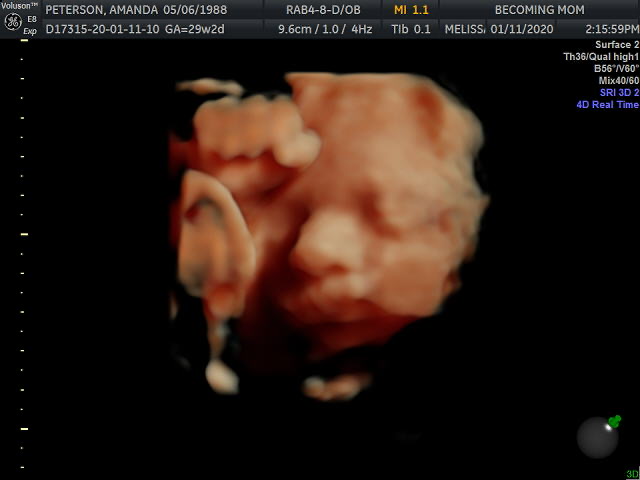

Hands down, the best part of this week was getting to see our baby girl via 3D/4D Ultrasound! Justin bought me a session at Becoming Mom as a Christmas gift, so he, my mom and I went on Saturday to see our sweet girl.

In addition to the unicorn, we got 26 photos and a video as a result of our visit (which I promptly forwarded on to all our family members and a few friends!). Her hand and her knee were up by her face the entire time, and the technician kept poking my belly to get her to move them. She would oblige, for two seconds, and then bring them right back up. Stubborn girl!

I am so obsessed with her little squishy nose and those cheeks!!! I can hardly believe that this precious face is a product of Justin and me. Reproduction is incredible. She’s so perfect, and now I’m even more anxious to meet her.